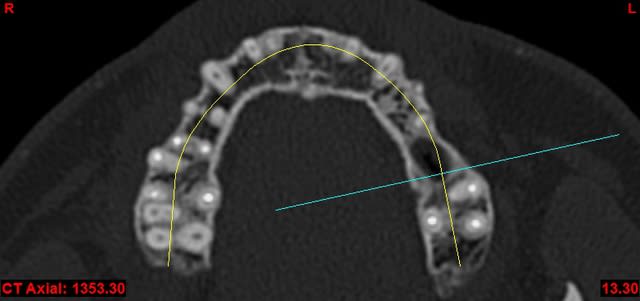

je dois pratiquer un rehaussement de plancher sinusien par volet latéral et je ne sais comment gérer le décollement de la membrane de Schneider au niveau de la communication bucco sinusale

Dès le départ, je m'inquiète au niveau du décollement du lambeau sur la CBS, on risque de déchirer à ce moment là

je joins quelques captures pour vous faire une idée

je ne vois pas de septum dans la zone de comblement

pourrais-tu préciser?